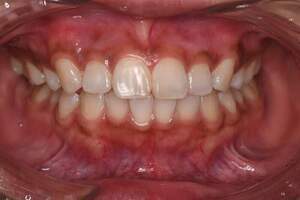

歯石除去・オフィスホワイトニング

治療前

治療後

| 年齢 | 30歳・女性 |

| 主訴 | クリーニング・歯を白くしたい |

| 治療内容 | 歯石除去・オフィスホワイトニング |

| 治療期間 | 60分×2回 |

| 費用 | 歯石除去 約2,000円 オフィスホワイトニング2回 6,600円(自費 診療) |

| リスク・副作用 | ・歯ぐきの炎症が強いと歯石を取る際に出血することがあります ・歯と歯の間に隙間ができるので、息が漏れ発音しにくいと感じることがあります ・歯ぐきの炎症が軽減すると歯ぐきが引き締まり、歯が長く見えることがあります ・ホワイトニングの効果は永久的なものではなく徐々に色戻りが起こります ・ホワイトニング後は歯の表面の水分量が一時的に少なくなりしみることがあります ・ホワイトニングは自費診療の施術です |